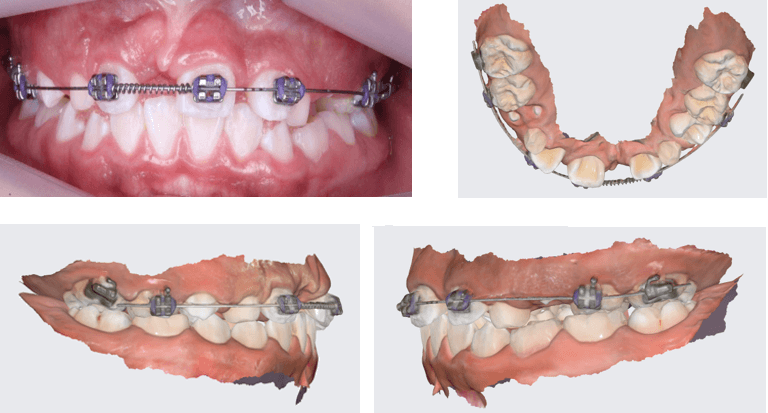

Después del retiro de ortodoncia interceptiva para realizar la tracción del IC 1.1, se realizó un control a los 6 meses para verificar los resultados del tratamiento. En esta cita se hizo una prueba de sensibilidad pulpar con cloruro de etilo con respuesta positiva, una radiografía periapical de control (Fig 29) así como la fotografía intraoral de frente (Fig 30) y un escaneo digital (Fig 31 y 32 ). En la radiografía periapical se observa ya un proceso de formación de hueso alveolar alrededor de la raíz del diente traccionado, incluida la formación de lámina dura como cortical alveolar.

Fig 29. Rx periapical N5 - Fig 30. Fotografía de control 6 meses después de retiro

Fig 31 y 32. Imágenes de escaneo digital intraoral, control 6 meses.